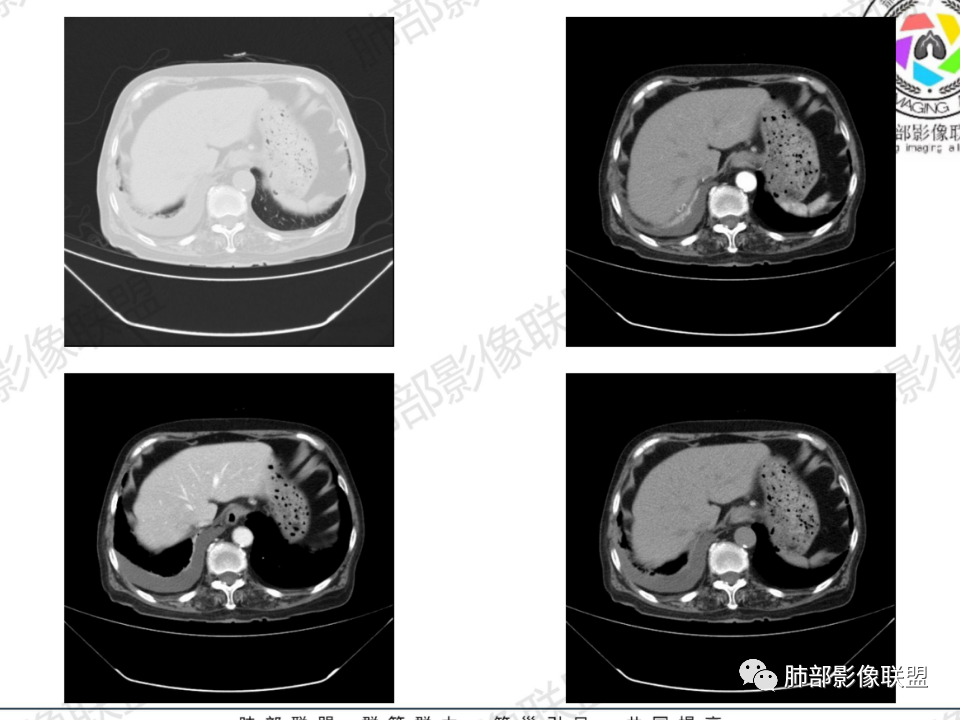

临床信息:老年女性,亚急性病程,咳嗽发热。有激素使用史。既往有淋巴结结核病史。肿瘤标记物Ca125升高。血沉升高,C反应蛋白轻度异常。 影像所见:右侧胸廓相对狭小,右肺上叶不规则团块影贴附纵隔旁,轻度分叶,整体密度较均匀,偶见钙点。

纵隔及双肺门见钙化淋巴结。心包积液,右侧胸腔积液(提示存在活动新病灶)。双侧胸膜下见多发斑点状钙化,胸廓变形(提示存在结核基础病变可能)。 诊断意见:综上,右肺上叶块状影更符合继发性肺结核。 最后小结:既往诊断淋巴结结核,提示已治愈。近2年服用激素,可疑诱导结核复燃,也可引起发热。纵隔肺门淋巴结肿大钙化,压迫支气管,右肺上中下叶支气管均狭窄,所以引起喘息咳嗽。尖段支气管受累闭塞,导致肺不张、支气管粘液栓,出现条状无强化区。病变累及胸膜,导致结核性胸膜炎并胸水,引起右侧胸痛。实验室检查血沉快,CA125高,低蛋白,均符合结核。下一步,建议支气管镜尖段支气管刷检并抗酸染色。(本段摘自於雄老师精彩发言)